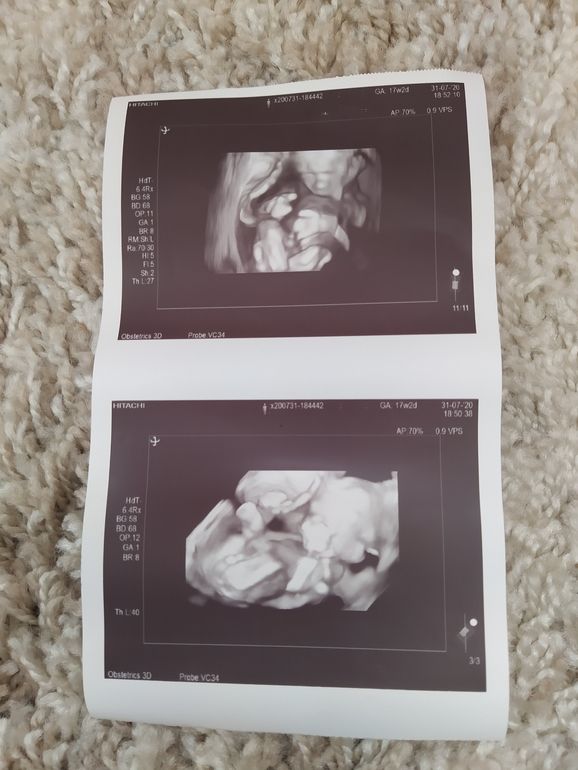

Вот мой сынок в 17+2 Изображение

24.07.2022